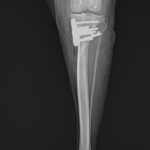

膝蓋骨内方脱臼 グレード4

小型犬の膝蓋骨内方脱臼(MPLグレード4)に対する整復依頼があった。徒手によって膝蓋骨が大腿骨滑車内に完納しない、つまり重症である。BRTにより大腿骨滑車形成術を行い、内側広筋の筋膜リリース、パテラを滑車に戻した状態で余剰関節包の再建術を実施。脛骨粗面を骨切り、大腿四頭筋〜膝蓋骨〜脛骨粗面〜足根関節のアライメント調整を行い仮固定ピンによりT.T.Tの移動幅を決定。5.0mmのスパイク形状のスペーサーでLateralizationを行った。1.5 Staggered Locking Patella Plate for T.T.Tを利用し、強固に粗面の固定術を実施。最後に骨切り部位にBRTで得られた海綿骨を移植し終了。日本ではまだ馴染みの少ない術式ではあるが、ドイツを中心にヨーロッパにおいて認知されはじめている。